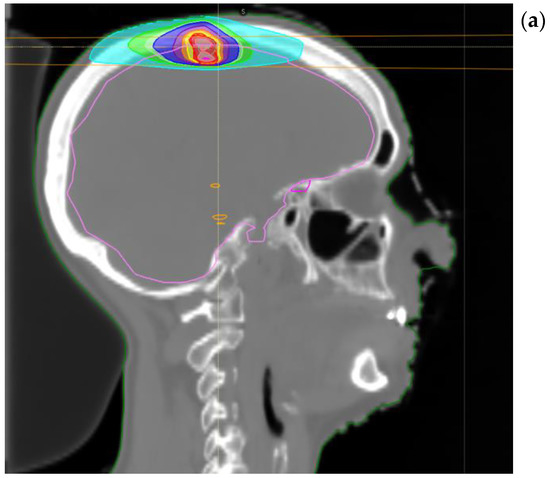

Her oncological history begun in 2017 when she was submitted to upper left lobectomy and homolateral hilar nodal sampling (May 2017) with pathologic report positive for solid pleomorphic neoplasm with spindle and giant cells. The final pathological stage was pT2a R0 pN0 (0/3) cM0. Adjuvant CHT with cisplatin and vinorelbine was administered and concluded on September 2017. During regular follow-up, the patient had a parenchymal relapse on the right lung so that in February 2018 she underwent double atypical right lung resection (dorsal segment of the upper lobe and lateral segment of the lower lobe). The pathological specimen was positive for invasive adenocarcinoma with papillary and solid growth, final stage pT2 pNx. The patient was followed up until July 2019 when an 18 fluor-deoxy-glucose PET-CT scan showed mediastinal recurrence in the right lower paratracheal area (station 4R), close to the bronchial bifurcation. Endobronchial ultrasound (EBUS) confirmed the diagnosis of nodal lung adenocarcinoma recurrence with Programmed Death-Ligand1 (PDL-1) expression 60% and wild type for oncogene alterations. During the multidisciplinary discussion, concomitant CHT-RT with radical intent was proposed. In September 2019 she underwent two cycles of CHT with cisplatin 80 mg/m2 and pemetrexed 500 mg concomitant with thoracic RT. The total dose delivered to the right hilar, paratracheal (4R, 11R), and subcarinal (station 10) nodes was 60 Gray in 30 fractions using Tomotherapy@. (Figure 1). All treatments delivered were well tolerated with patient referring G2-G3 dysphagia and esophageal mucositis so the patient was fed by parenteral nutrition for a week. Her quality of life during this first phase of treatment mildly decreased for a while, but the patient fully recovered after two weeks from the end of RT treatment.

Figure 1.

Treatment plan for mediastinal relapse.